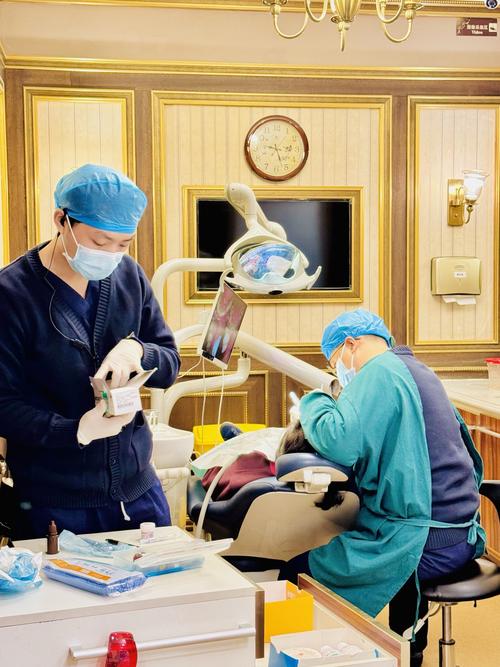

(图片来源网络,侵删)

(图片来源网络,侵删)- 术前准备:拍摄头颅侧位片、CBCT(三维重建)、取模型,进行头影测量分析,模拟手术效果;

- 手术实施:在全麻下进行,根据术前设计截骨、移动颌骨,用钛板钛钉固定(可吸收材料也可选择,费用略高);